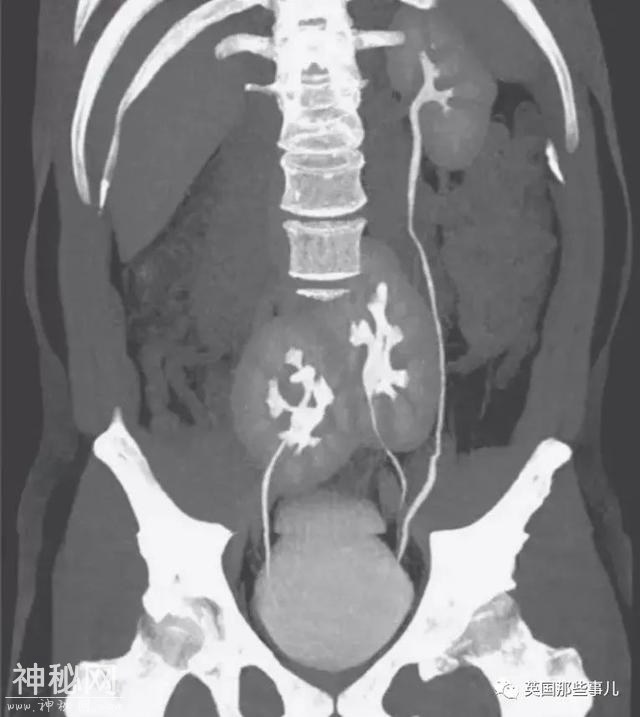

7,第三个肾脏

《新英格兰医学杂志》在5月报道了一个病例。一名38岁的巴西男子因为严重的背部疼痛寻求治疗,CT扫描显示,他患有腰椎盘突出。

这个病症不奇怪,但他的医生在扫描图片上看到古怪的一幕:该男子不像普通人那样拥有两个肾,而是有三个。

一个外观正常的肾脏位于他的左侧,两个融合的肾脏位于骨盆附近。

绿尿,膀胱酿酒,心脏插针?2020年度诡异病例盘点,简直大开眼界-7.jpg

通常,每个肾脏通过输尿管和膀胱连接。在该男子的身体里,多出来的肾的输尿管和左侧正常肾的输尿管相连。

虽然看上去奇怪,但该男子没有任何肾脏引发的症状,三个肾都工作正常。

最后,医生们没有对多出来的肾进行额外的医疗,只给了他口服止痛药来治疗背部疼痛。